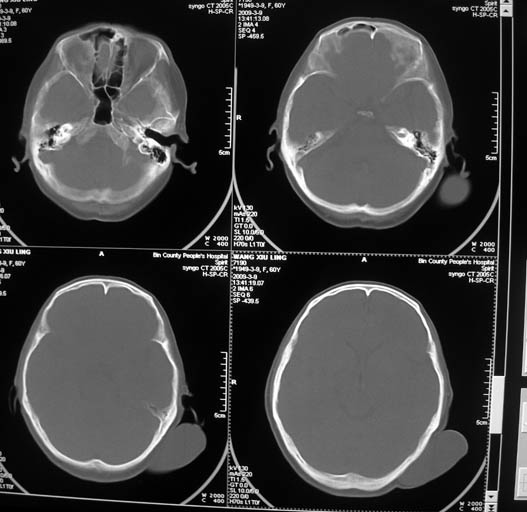

标题: CT18574:女,60岁,头部肿物。 [打印本页]

标题: CT18574:女,60岁,头部肿物。

女,60岁,头部肿物。ct值为12hu。

左枕部软组织影,考虑皮样囊肿?最好穿刺!

考虑皮脂腺瘤或皮样囊肿,建议穿刺活检!